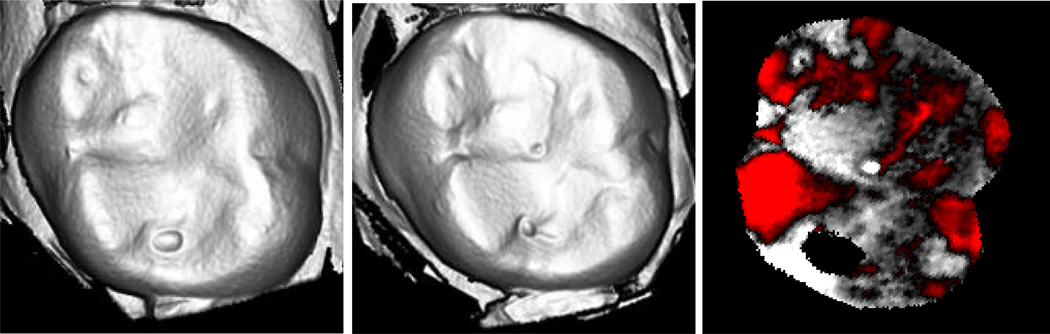

Figure 4.

Laserscan 3D images of a glass-ceramic veneer restoration for one lower left, first molar: a) baseline; b) after one year; c) superimposed subtractive image. The red areas indicate less surface material, i.e., the most wear.

The mean wear of enamel antagonists (141 µm) is represented in laser scans (Figure 6) for a maxillary right first molar that opposed a veneered surface. The micrographs of the same specimen (Figure 7) highlight the surface roughening at the wear facets. However, the wear rates on the crown and tooth opposing these representative samples were not significant.

Figure 6.

Laserscan 3D images for one natural enamel, maxillary, right first molar antagonist (opposed ceramic crown): a) baseline; b) after one year; c) superimposed subtractive image. The red areas represent enamel wear on buccal and lingual cusps after year 1.